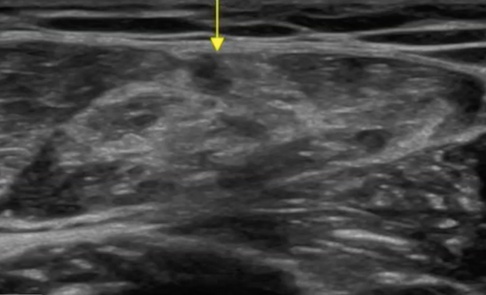

Las roturas miofasciales son más fáciles de resolver, por lo general, tienen un mayor sangrado, pero el proceso de cicatrización es menos agresivo.

Recuerda que si detectas una sufusión hemática de gran tamaño, debes derivar al paciente para que se la extraigan.

No hacerlo retrasará el proceso de recuperación y puede predisponer al desarrollo de efectos secundarios como es la miosotis osificante.